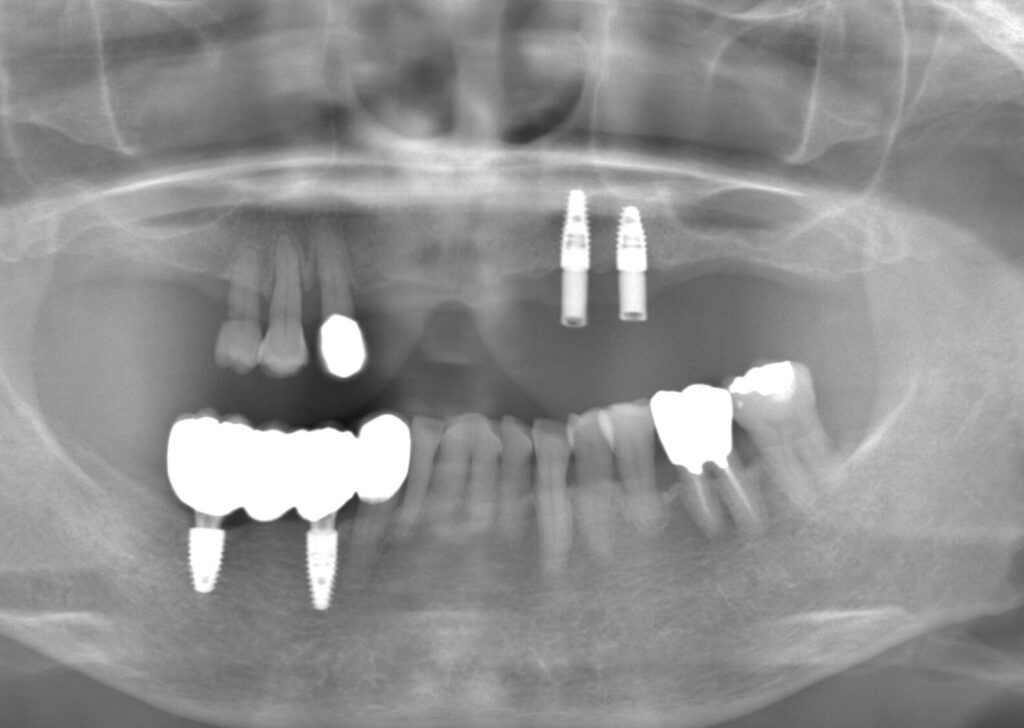

今回は入れ歯の相談で来院された患者さんです。

元々、入れ歯を使用していたが、歯にかける金具が見えるのが気になるとの事です。

治療前の口腔内写真です。

下の歯は2本のみ残存しており、その部分に入れ歯をかけている状態でした。

今回は歯の本数が少ないため、ブリッジを選択することができないのと、治療期間、金額の面を考慮し目立たない入れ歯を検討することになりました。